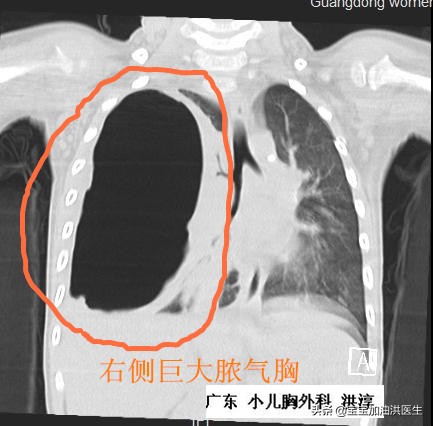

二、感染。感染,特别是胸腔内的感染,比如肺炎,会增加肺组织的渗液,影响胸水的分泌-吸收平衡,进一步导致胸腔积液。这种情况往往在婴幼儿中会相对多见,胎儿-新生儿方面相对就少一些。像一些几岁的孩子,出现发热、咳嗽一段时间,有些就可能出现胸腔积液,尤其是支原体肺炎感染的小娃。(就如下图,就是一个先天性肺囊肿合并感染,出现胸腔积液的情况-当然,这个积液不是主要问题)